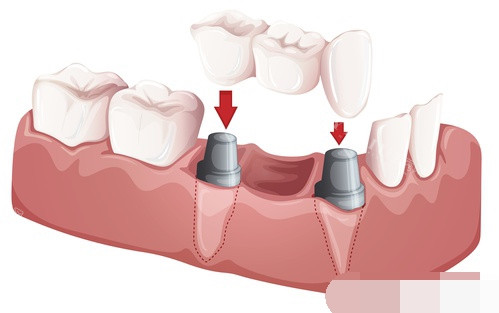

| 固定义齿 | 3500-9000起 |